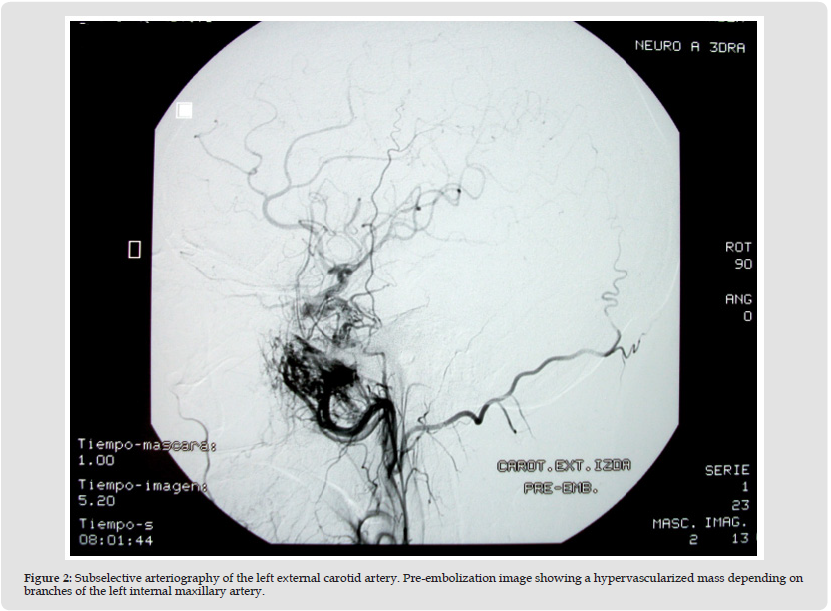

Due to aesthetic concerns and continuous growth, surgical excision was recommended. Before the surgery, a subselective arteriography was performed. In the pre-embolization images, a hypervascularized mass depending on branches of the left internal maxillary artery was identified (Figure 2). The tumor was embolized using polyvinyl alcohol microparticles, and liquid coils in the left internal maxillary artery’s pedicle, showing significant decrease of the lesion in the post-embolization images (Figure 3). One day following embolization, the patient underwent surgical removal of the hemangioma using a hemicoronal approach with preauricular and submandibular incisions. External carotid artery was temporally clamped due to the possible intraoperative bleeding. The left temporalis muscle within the angiomatous mass was then totally excised to the coronoid process, after removal of the zygomatic arch and ligation of the left maxillary artery at the liquid coil’s level. The zygomatic arch was then replaced, and the defect filled with a temporal polyethylene implant. On the histological examination, the tumor was composed of a large number of interconnecting endothelial-lined vascular spaces in skeletal muscle, consistent with an intramuscular haemangioma of the capillary type. The patient had an uncomplicated postoperative recovery, achieving favorable functional and cosmetic outcomes. Nine years after the surgery, there are no signs of recurrence